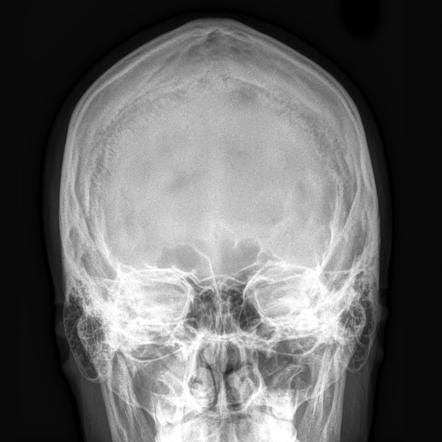

X-ray: x-rays, or “radiographs” use really high energy photons, that’s the same thing they were talking about when we’re talking about Light. Photons can be Red, photons can be Blue, photons can be really low power radio waves, and they can be really high power x-rays. When you take a really high power x-ray, which is a photon vibrating very very fast, with a higher frequency than even ultraviolet light, it can penetrate through the human body. Some of those x-rays will get absorbed on the way through, and others will not.

What determines whether they will go all the way through, and eventually hit a photographic plate on the other side?7 Well, if they hit something dense they’re more likely to be absorbed. If those photons hit something less dense, they cruise through. Bones are dense. Thus they are white on an x-ray because all those x-ray photons got absorbed and didn’t go through to the photographic plate on the back. When passing through the body containing muscle and blood vessels and brains and stuff, less of them get absorbed, and more of those photons hit a photographic plate. Like visual spectrum photons hitting a film negative, it gets darker. When we see x-ray radiographs, we’re looking at negatives, and unlike in photography, we don’t bother to flip the image so that white gets dark to the eye.

But that’s how we get an x-ray machine to make an x-ray picture. And then doctors can look at that and see what’s inside your body. We get the best resolution of bones — they’re the most dense.